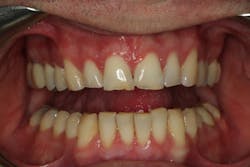

Through working with Darren, we were able to provide the necessary treatment to obtain the five requirements of occlusal stability. He now has stable stops on all teeth, anterior guidance in harmony with the envelope of function, anterior teeth that provide immediate posterior disclusion in protrusive, and he no longer has working and balancing side excursive interferences.

Overall, the case closely followed our treatment plan blueprint because of proper diagnosis and planning. Darren was comfortable with his envelope of function, occlusal stability was restored, and he was thrilled with his natural, esthetically pleasing smile.